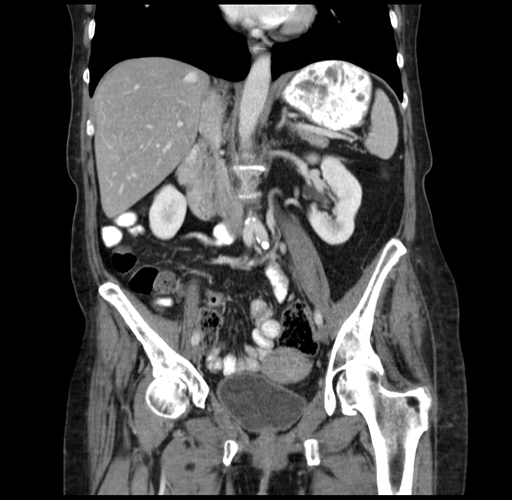

Pre-Chemo: Coronal Venous